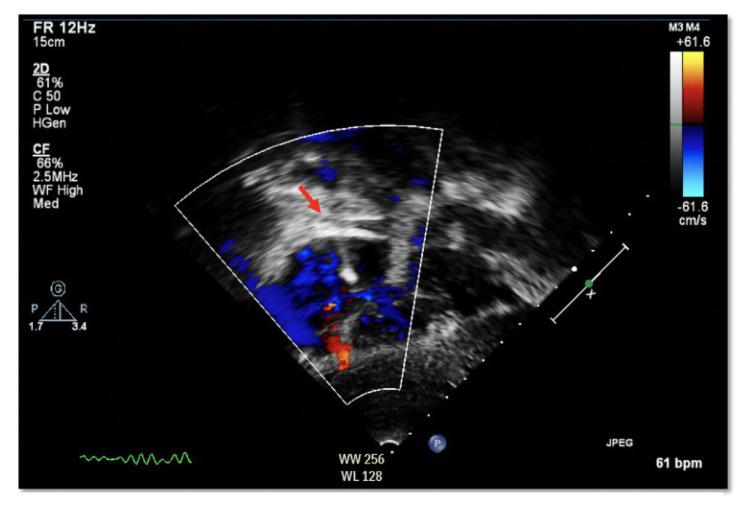

Transcatheter closure of septal defects using specialized devices is a common procedure that has a high success rate. Embolization of Atrial septal defect devices is a known complication seen at a rate of 0.5%. We report a case of late ASD device occluder embolization immediately after brain MRI with clinical consequences and intraoperative evidence of right atrial wall thermal injury. To our knowledge Atrial septal occluder (ASO) device embolization post magnetic resonance imaging (MRI) was not reported before, although theoretically possible and that's why six to eight weeks post device implantation MRI is prohibited even with current MRI compatible devices.

使用专门装置经导管闭合间隔缺损是一种成功率很高的常见手术。房间隔缺损装置的栓塞是一种已知并发症,发生率为0.5%。我们报告一例在脑部MRI检查后立即发生的晚期房间隔缺损装置封堵器栓塞病例,该病例产生了临床后果,术中发现右心房壁有热损伤迹象。据我们所知,尽管理论上有可能,但此前尚未有磁共振成像(MRI)后房间隔封堵器(ASO)装置栓塞的报道,这就是为什么即使使用目前与MRI兼容的装置,在装置植入后六至八周内仍禁止进行MRI检查。